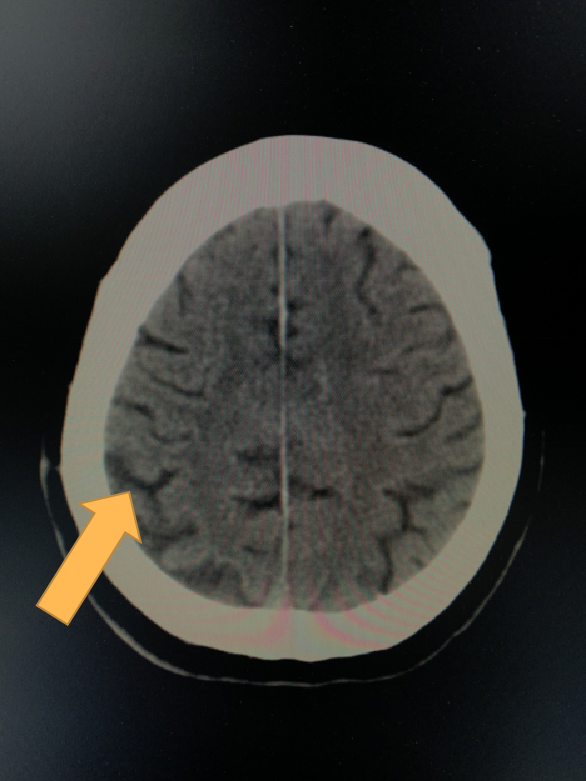

之所以排在第一位,是因为一般60岁以上人群做CT检查后经常会出现这种征象。大部分情况下它是一种生理性改变,和人老了头发会变白,会有皱纹是一个道理)

60岁体检女性。可以看到与正常人比,脑沟增宽了